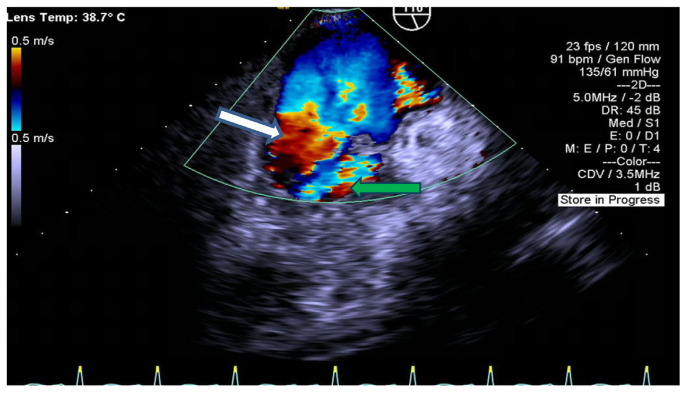

Aerococcus urinae is an alpha-hemolytic gram-positive catalase-negative coccus that typically causes urinary tract infections. It has been rarely implicated in other invasive infections such as endocarditis, bacteremia, peritonitis, meningitis, and vertebral osteomyelitis. There are approximately 50 reported cases of A. urinae infective endocarditis in literature. We present a rare case of a 64-year-old male who was found to have a urinary tract infection, bacteremia, and endocarditis caused by A. urinae.